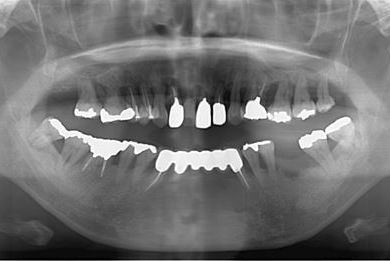

インプラントの症例写真 IMPLANT

骨再生スピードインプラント治療+セラミック治療

| 性別/年齢 | 女性 / 43歳 | ||||||||||||||||||||||||||||||||

| 主訴 | 骨が薄いが、インプラント治療を希望。 | ||||||||||||||||||||||||||||||||

| 治療方針 | 抜歯と同時にインプラントを埋入し、治療期間を短縮する。ソケットリフトにて上顎洞を拳上し、インプラント治療を可能にする。 | ||||||||||||||||||||||||||||||||

| 治療内容 | インプラント9本(抜歯即日スピードインプラント、ソケットリフト、テンポラリーインプラント+仮歯)、メタルボンドセラミッククラウン18本、メタルボンドセラミックブリッジ6本(メタルボンド用土台6本)、遊離歯肉移植術 | ||||||||||||||||||||||||||||||||